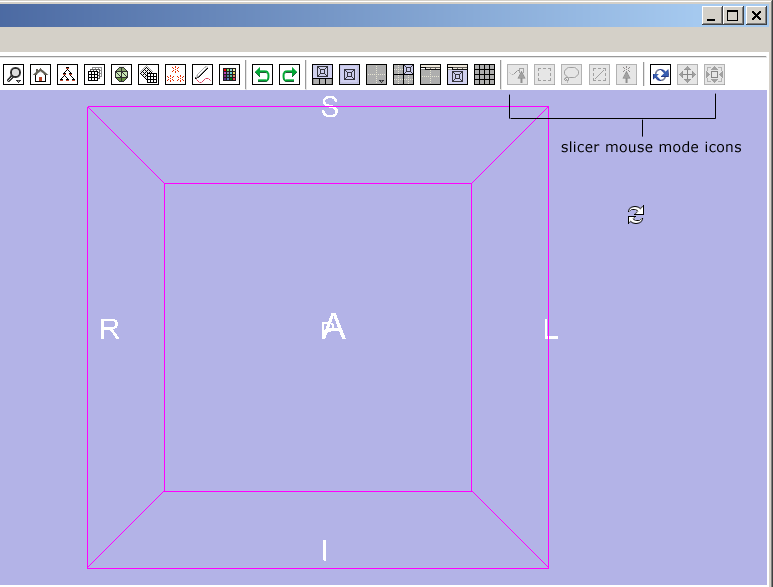

Simple workflow storyboard

Below is how a user would use the mouse-mode interface to tumble, track and dolly the camera to get the 3D View to look the way they like, and then put down three fiducial points and adjust their position.

A novice user's workflow is described and an expert user's workflow using for the same simple task is given for comparison.

Slicer mockup and GUI screenshots from other packages:

Below is how the proposed interface using these icons would appear; Slicer would start up in mouse-tumble mode, showing the tumble cursor over the 3D Viewer. Beneath that image are SketchUp's interface, and Maya Interface, and the proposed Slicer mouse-mode icons (selected and deselected) as proposed. Maya's mouse modes switch between object transforms (translate, rotate and scale), object or region select, and an extrude function. SketchUp's mouse-mode icons switch between view transforms (translate, rotate, zoom) and an object extrude function.